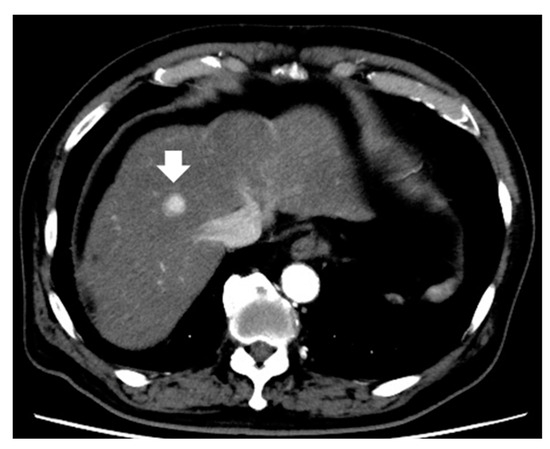

- Motosugi, U.; Murakami, T.; Lee, J.M.; Fowler, K.J.; Heiken, J.P.; Sirlin, C.B. Recommendation for terminology: Nodules without arterial phase hyperenhancement and with hepatobiliary phase hypointensity in chronic liver disease. J. Magn. Reson. Imaging 2018, 48, 1169–1171. [Google Scholar] [CrossRef] [PubMed]

- Motosugi, U.; Bannas, P.; Sano, K.; Reeder, S.B. Hepatobiliary MR contrast agents in hypovascular hepatocellular carcinoma. J. Magn. Reson. Imaging 2015, 41, 251–265. [Google Scholar] [CrossRef]

- Kim, T.H.; Woo, S.; Han, S.; Suh, C.H.; Lee, D.H.; Lee, J.M. Hepatobiliary phase hypointense nodule without arterial phase hyperenhancement: Are they at risk of HCC recurrence after ablation or surgery? A systematic review and meta-analysis. Eur. Radiol. 2020, 30, 1624–1633. [Google Scholar] [CrossRef]

- Lee, D.H.; Lee, J.M.; Lee, J.Y.; Kim, S.H.; Kim, J.H.; Yoon, J.H.; Kim, Y.J.; Lee, J.H.; Yu, S.J.; Han, J.K.; et al. Non-hypervascular hepatobiliary phase hypointense nodules on gadoxetic acid-enhanced MRI: Risk of HCC recurrence after radiofrequency ablation. J. Hepatol. 2015, 62, 1122–1130. [Google Scholar] [CrossRef] [PubMed]

- Iwamoto, T.; Imai, Y.; Igura, T.; Kogita, S.; Sawai, Y.; Fukuda, K.; Yamaguchi, Y.; Matsumoto, Y.; Nakahara, M.; Morimoto, O.; et al. Non-Hypervascular Hypointense Hepatic Nodules during the Hepatobiliary Phase of Gadolinium-Ethoxybenzyl-Diethylenetriamine Pentaacetic Acid-Enhanced MRI as a Risk Factor of Intrahepatic Distant Recurrence after Radiofrequency Ablation of Hepatocellular Carcinoma. Dig. Dis. 2017, 35, 574–582. [Google Scholar] [CrossRef] [PubMed]